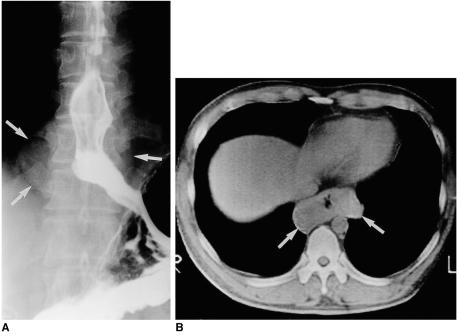

The tumors, surgical specimens of which ranged from 9 to 90 mm in diameter, were located in the upper (n = 1), middle (n = 5), or lower esophagus (n = 6). In ten of the 12 patients, chest radiography revealed the tumors as mediastinal masses. Esophagography showed them as eccentric, smoothly elevated filling defects in 11 patients and a multilobulated encircling filling defect in one. In 11 of the 12 patients, enhanced CT scans revealed a smooth (n = 9) or lobulated (n = 2) tumor margin, and attenuation was homogeneously low (n = 7) or iso (n = 4). In one patient, the tumor signal seen on T2-weighted MR images was slightly high.

Esophageal leiomyomas, located mainly in the middle or distal esophagus, are consistently shown by esophagography to be mainly eccentrically elevated filling defects and at CT, lesions showing homogeneous low or isoattenuation are demonstrated.